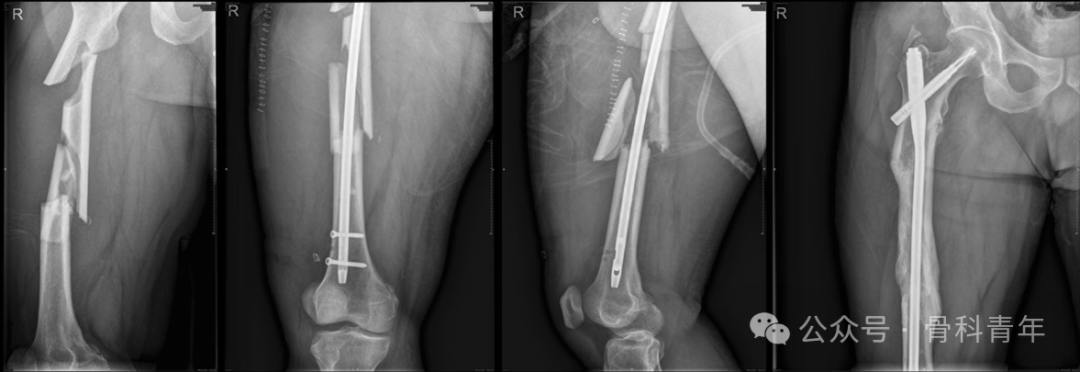

股骨干骨折

文章纳入了37例粉碎性股骨干骨折病例,16例行钢丝环扎辅助固定,21例行单纯髓内钉固定:

文章结果表明,钢丝环扎组,在骨科愈合时间,术后12月和24月HSS评分、HHS评分,骨折愈合率上均存在明显优势。建议对粉碎性股骨干骨折行钢丝环扎辅助固定。

在另一篇对股骨干粉碎性骨折钢丝环扎的固定研究中,尽管在骨折愈合率和并发症上未发现统计学差异,但钢丝组骨折复位较非钢丝辅助复位组好,且并不增加并发症风险。钢丝环扎具有非劣效应。